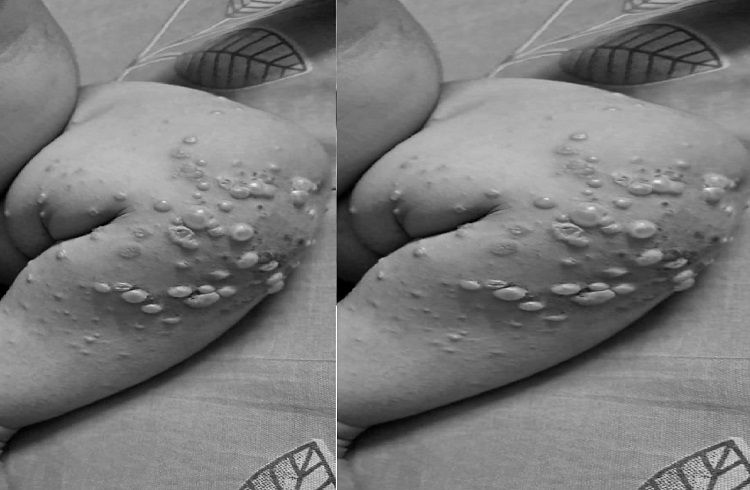

ಎನ್ಟಿಆರ್ ಜಿಲ್ಲೆಯ ಪೆನುಗಂಚಿಪ್ರೋಲ್ನಲ್ಲಿ ಮಗುವಿನ ದೇಹದಾದ್ಯಂತ ಗುಳ್ಳೆಗಳು ಮತ್ತು ತೀವ್ರ ತುರಿಕೆಯೊಂದಿಗೆ ವಿಚಿತ್ರ ಕಾಯಿಲೆಯಿಂದ ಸೋಂಕಿಗೆ ಒಳಗಾಗಿದ್ದು, ಇದು ಸ್ಥಳೀಯರು ಮತ್ತು ಅಧಿಕಾರಿಗಳನ್ನು ತೊಂದರೆಗೊಳಿಸುತ್ತಿದೆ. ಮಗುವಿಗೆ ಈ ವಿಚಿತ್ರ ಕಾಯಿಲೆ ಇದೆ ಎಂಬ ಪ್ರಚಾರವು ಜಿಲ್ಲೆಯಲ್ಲಿ ಕಳವಳವನ್ನುಂಟುಮಾಡಿದೆ. ಪರಿಸ್ಥಿತಿಯ ಗಂಭೀರತೆಯನ್ನು ಅರಿತುಕೊಂಡ ಜಿಲ್ಲಾ ಅಧಿಕಾರಿಗಳು ತಕ್ಷಣ ಪ್ರತಿಕ್ರಿಯಿಸಿ ಮಗುವನ್ನು ಚಿಕಿತ್ಸೆಗಾಗಿ ವಿಜಯವಾಡ ಸರ್ಕಾರಿ ಆಸ್ಪತ್ರೆಗೆ (ಜಿಜಿಹೆಚ್) ಸ್ಥಳಾಂತರಿಸಿದರು. ಚಿಕಿತ್ಸೆಯ ನಂತರ ಮಗುವಿನಲ್ಲಿ ಸೋಂಕು ಕಡಿಮೆಯಾಗಿದೆ ಎಂದು ವೈದ್ಯರು ತಿಳಿಸಿದ್ದಾರೆ.

చిన్నారులకు వైరల్ ఇన్ఫెక్షన్.. కాళ్లు, చేతులపై బొబ్బలు